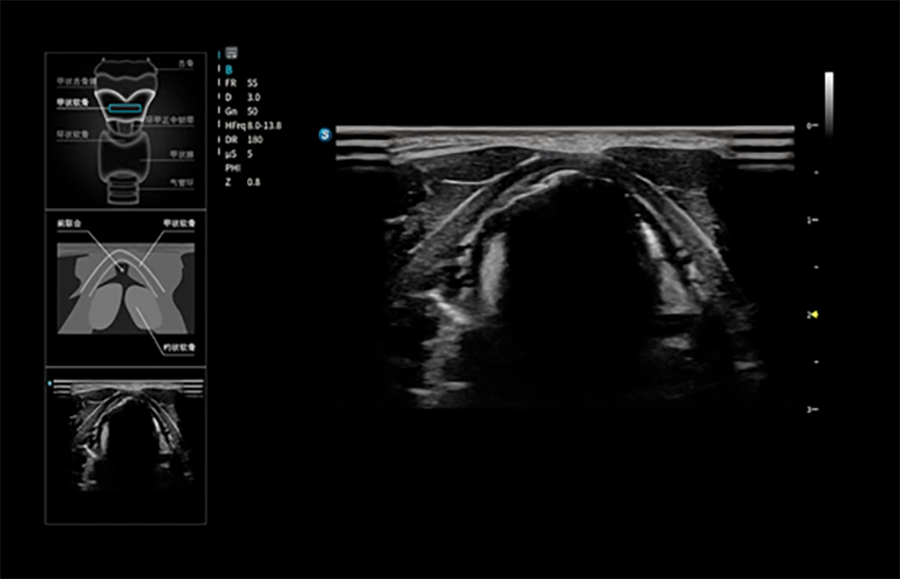

超声教学软件

通过智能引导、实时反馈与操作提示,全程指导医护人员掌握扫查技巧,成为年轻医生的“超声领航员”。